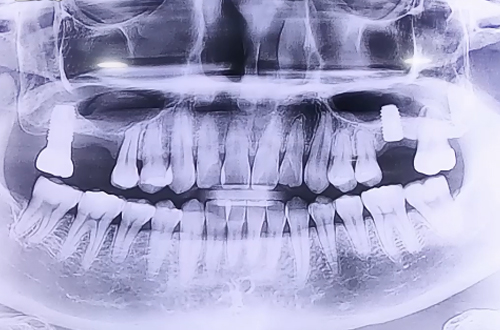

상악동거상술을 동반한 뼈이식 임플란트

치료 유형 상악동거상술 뼈이식 임플란트

상악동거상술을 동반한 뼈이식 임플란트로 추정되는 부분에 염증이 생기면서 반대편에 임플란트를 진행하기 위해 방문하신 환자분이십니다.

반대편 오른쪽 위에도 뼈가 조금 남아있는 상태였기 때문에 상악동거상술을 동반하여 뼈이식을 진행해 드렸습니다.

뼈이식 이후 임플란트까지 당일 식립해 드렸으며 뼈이식의 양이 많기 때문에 뼈들이 단단해지는 기간인 6개월 이상 충분히 기다린 뒤에 큰 어금니 모양의 이를 제작해 드릴 예정입니다.